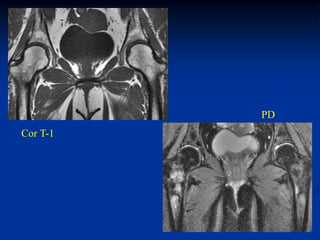

Case #1169.1                      Stress fractures

43 yr female on steroids for lupus with bilat hip pain for 6 months

Bone scan

PD

Cor T-1

Axial PD